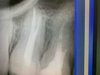

• Работа с дентальным рентгеном, радиовизиографом

Анализ прицельных рентген-снимков, ОПТГ, КТ.

Проведение и анализ снимков на визиографе и рентген-аппарате.